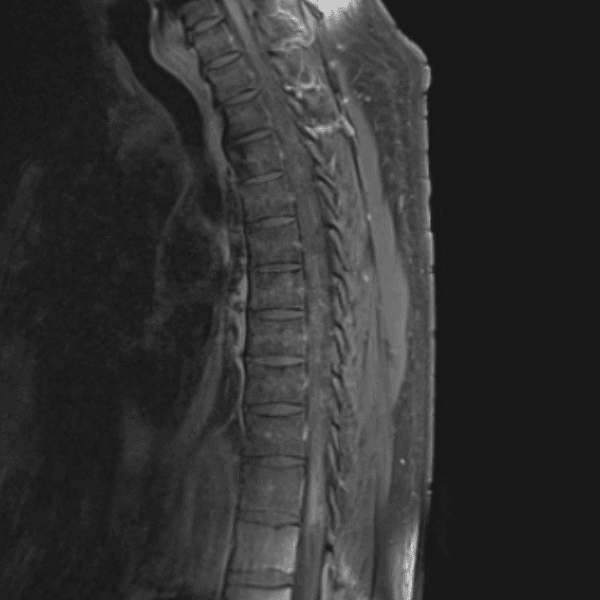

Simulates call by including subtle or difficult cases and some normals.

35 cases